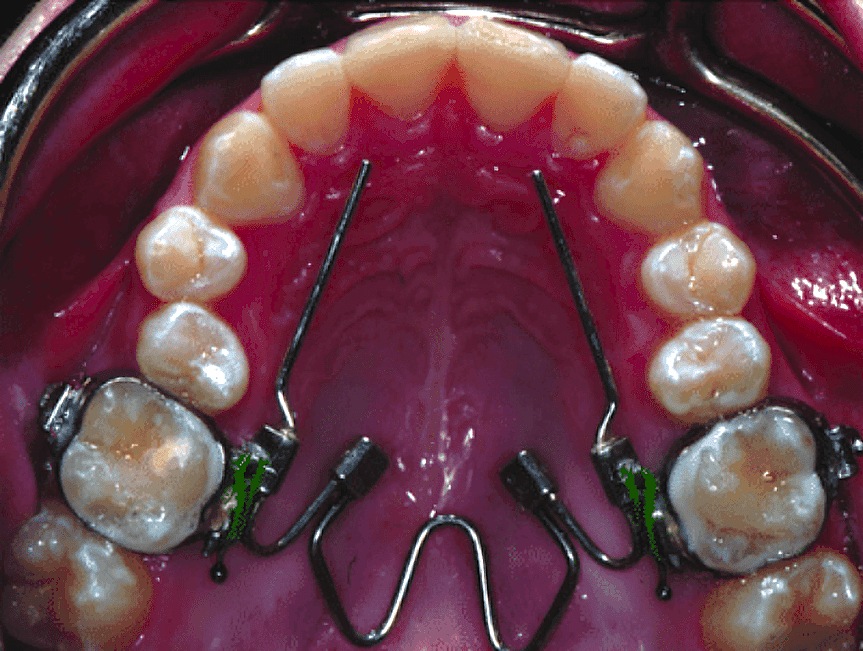

1. Space Maintainers

Photo by Nadia Mohamed – ResearchGate

Space maintainers are used when a child loses a baby tooth prematurely.

These devices physically occupy the space left by the lost tooth, preventing adjacent teeth from shifting into the gap and thus preserving the space for the permanent tooth to erupt properly.